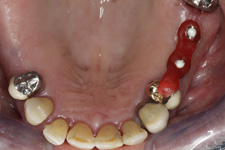

V případě chybění většího počtu zubů v postranních úsecích čelistí je možné ošetření pomocí implantátů, které nahradí ošetření pomocí snímacích náhrad kotvených na zbývajících zubech nebo patře.

Podmínkou je opět dostatečné množství kosti.

Protetické řešení může být pomocí můstku, který je kotvený na implantátech nebo pomocí jednotlivých korunek na implantátech.

V zásadě je možné do těchto můstků zařadit i přirozené zuby, zejména pokud je potřeba tyto zuby ošetřit proteticky

- korunkami. Korunky nebo můstky mohou být na implantáty nacementovány nebo přišroubovány.

Zdravé zuby zůstanou zachovány a přitom náhrady jsou pevné, jako na vlastních zubech